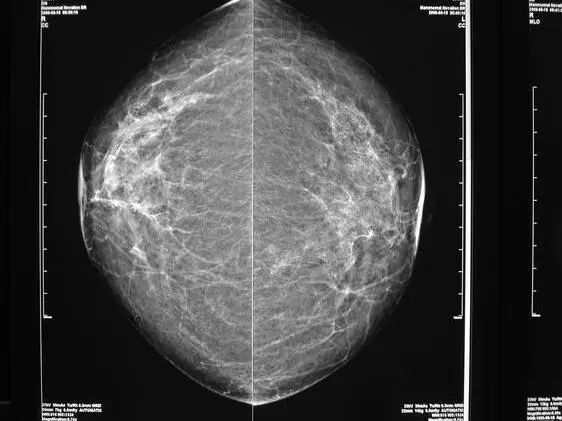

什么是钼靶检查?

钼靶广泛应用于各种乳腺疾病的筛查和诊断,是利用 X 光投射到乳房上面,穿过乳房以后将它成像在含钼的底板上,然后对乳房的影像进行一个分析诊断,和乳腺超声一样,是一种无创性检查。

乳腺钼靶X线摄影检查能清晰显示乳腺各层组织,可以发现乳腺增生,各种良恶性肿廇以及乳腺组织结构紊乱,可观察到小于0.1毫米的微小钙化点及钙化簇,是早期发现,诊断乳腺癌的最有效和可靠的方式,尤其对于临床不能触及的,以微小钙化簇为唯一表现的早期乳腺癌具有特征性的诊断意义。它的特点是可以检测出医生触摸不到的乳腺肿块,特别是对于大乳房和脂肪型乳房,其诊断性可高达95%,对于以少许微小钙化为唯一表现的T0期乳腺癌(临床门诊阴性),也只有凭乳房X线检查才能被早期发现和诊断。

常规的乳腺X线检查包括2个位置的拍片,头足轴位(CC位)和内外侧斜位(MLO位),通过这两种标准位置照片,可以保证乳腺相对活动的下部以及相对固定的上部和内侧部分充分成像。当然必要时也有一些特殊的方位,比如乳沟位,局部点压等。

(MLO位:内外侧斜位)

(CC位:水平位)

为了获得质量良好的影像,必须对乳房进行充分的压迫,充分的压迫会增加图像的对比度,并且降低辐剂量,也能使得乳腺厚度均一,压迫还能减少乳房运动并最小化组织的重叠,从而提高诊断质量。因此拍片的时候因对乳腺的挤压,可能会有一定不适,但一般都能接受,拍好后就会放开,不适会自然缓解。